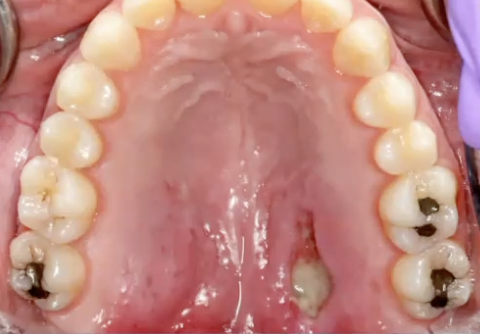

<p>What is this?</p>

What is this?

Pleomorphic adenoma in the palate